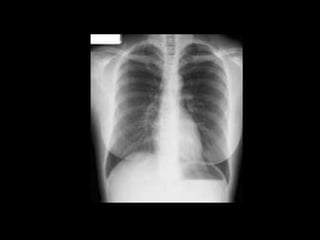

This document provides an overview of normal musculoskeletal imaging. It discusses basic x-ray concepts and densities. It then reviews normal anatomy as seen on x-rays of the skull, spine, pelvis, chest, and extremities. Key anatomical structures are labeled on example x-rays for the shoulder, hip, knee, and foot. Quizzes are included to test recognition of anatomical structures and patient age based on x-rays.